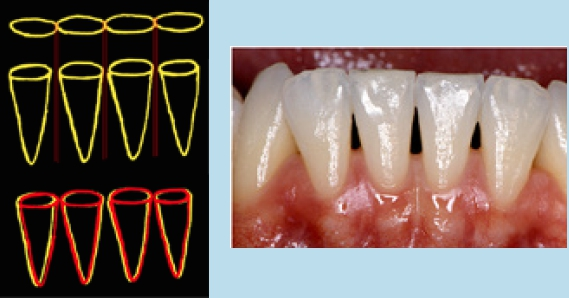

Hier muss zwischen einer Schmelzreduktion an korrekt stehenden Zähnen und einer an malpositionierten Zähnen unterschieden werden. Bei korrekt angeordneten Zähnen bewirkt die Schmelzreduktion eine Verkleinerung in Höhe und Breite des Approximalkontaktes. Dies führt zu einer Vergrößerung des Papillenplateaus, das mit nichtkeratinisiertem Epithel bedeckt ist und gegenüber parodontalen Erkrankungen empfindlicher ist als das keratinisierte Epithel [26]. Diesem Problem muss mit guter Mundpflege begegnet werden (Abb. 5). Bei einer Schmelzreduktion an malpositionierten Zähnen wird die Größe des Approximalraums nicht verringert, sondern leicht vergrößert, wenn man beachtet, dass das Ausmaß der Reduktion das des Überlappens nicht überschreiten darf (Abb. 6). Jedoch sollte man nicht vergessen, dass das Alignment durch Schmelzreduktion die normale Anatomie des Kontaktpunktes und des Zahnzwischenraums nicht wiederherstellt. Berücksichtigt wurden hier folgende Zahnpositionen:

Die Zahnschmelzreduktion hinterlässt an den betroffenen Zähnen Rillen von einer Tiefe, die zwischen 10 und 30 ?m liegt. Die Anwendung von Diamantstreifen hinterlässt dabei die raueste Oberfläche [17]. Eine dadurch erhöhte Kariesfrequenz konnte allerdings nicht nachgewiesen werden. Zachrisson begründet diese Tatsache damit, dass es sich bei dem Zahnschmelz um eine „dynamische Oberfläche“ handelt, die sich remineralisiert und stabilisiert [32]. Eine Studie von Mangoury [18] konnte elektronenmikroskopisch nach 9 Monaten eine Remineralisation nachweisen. Als Grundsatz der Schmelzreduktion muss jedoch gelten, die Schmelzdicke maximal auf die Hälfte zu reduzieren, um einen ausreichenden Schutz des Zahnes zu gewährleisten. Eine Reduktion des Zahnschmelzes bei korrekt stehenden Zähnen verkleinert den Interdentalraum und damit das Septum. Bei eng stehenden Zähnen wird der Interdentalraum größenmäßig erhalten bzw. vergrößert, wenn die Reduktion die Überlappung der Zähne nicht überschreitet. Je schmaler der interdentale Knochen ist, desto unempfindlicher ist er gegenüber parodontalen Erkrankungen. Die Widerstandsfähigkeit des interradikulären Knochens steigt bei Reduktion, während die Empfindlichkeit des parodontalen Gewebes steigt.

Es konnte ein Zusammenhang zwischen dem Knochenverlust bei parodontalen Erkrankungen und der Verbreiterung des Interdentalraums nachgewiesen werden. Studien von Betteridge [4] und Boese [6] zeigten keine Verringerung des Alveolarkammes bzw. sogar bessere Gingiva-Indizes nach approximaler Schmelzreduktion bei UK-Frontzähnen. Crain und Sheridan [9] fanden ebenfalls keinen signifikanten Unterschied bei lateraler Reduktion. Eine Verkleinerung des Approximalraums führt weiterhin zu einer Vertiefung des Papillenplateaus und begünstigt dadurch eine vermehrte Plaqueretention. Außerdem steigt die Empfindlichkeit des dünnen, nichtkeratinisierten Epithels, die zusammen mit der Verringerung des Bindegewebes zu parodontalen Problemen führen kann.